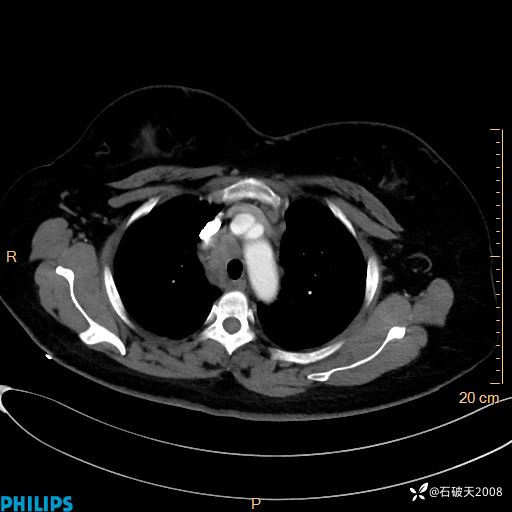

动脉期